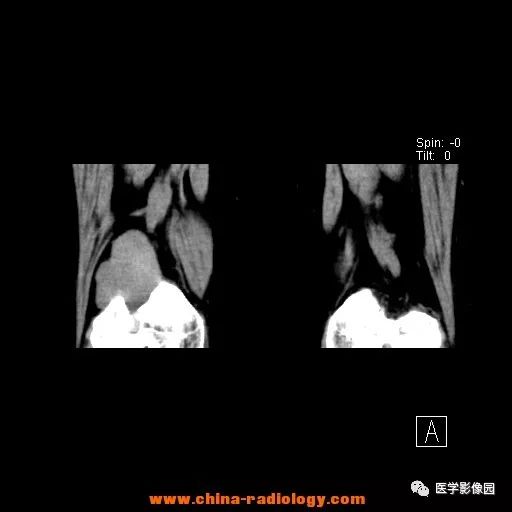

患者女性,29岁,右膝关节痛疼3月余,局部无红肿。

影像学表现:右股骨远端外后方可见局限性骨质破坏及软组织肿块,边界清楚。

病理结果:梭形细胞瘤